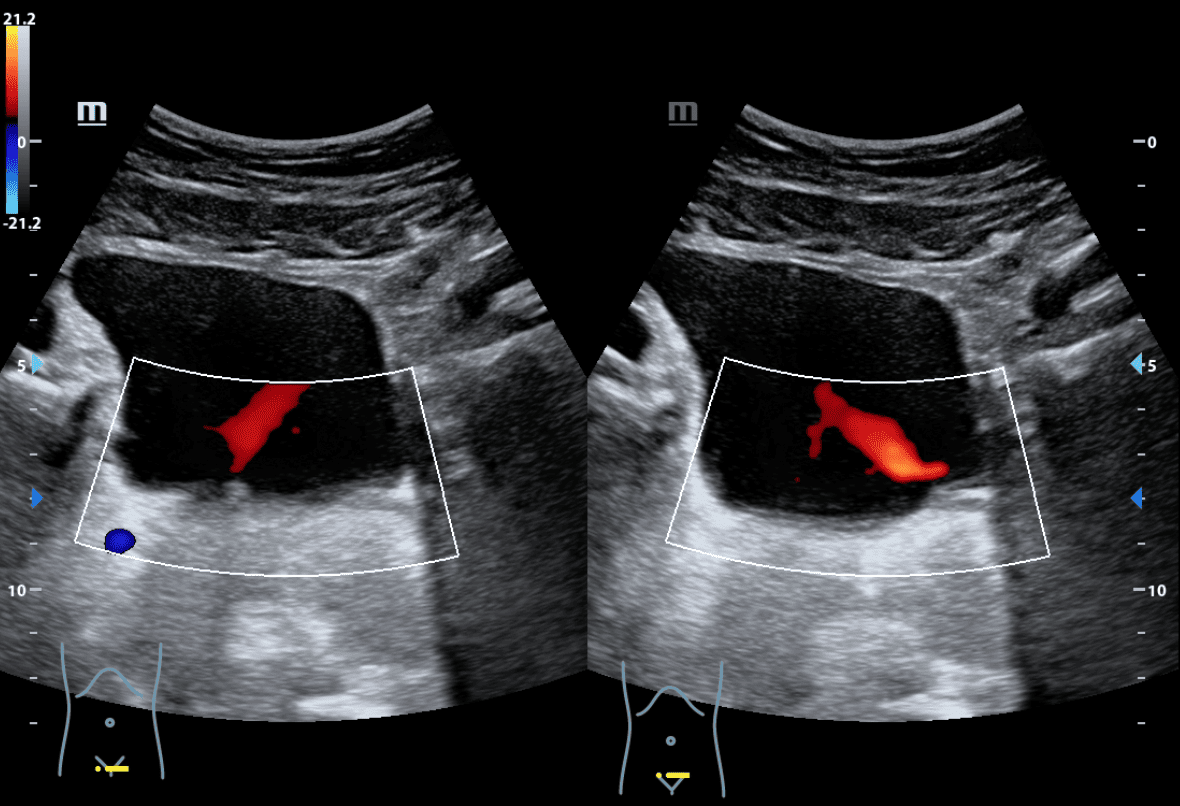

Se realiza ecografía en la misma consulta a fin de descartar cólico renal complicado.

Se observa a nivel de riñón derecho imagen anecogénica en seno renal, con afectación de cálices y desestructuración de la cortical renal. Riñón izquierdo sin hallazgos patológicos. Jets ureterales sin alteraciones. Impresiona de hidronefrosis grado IV.